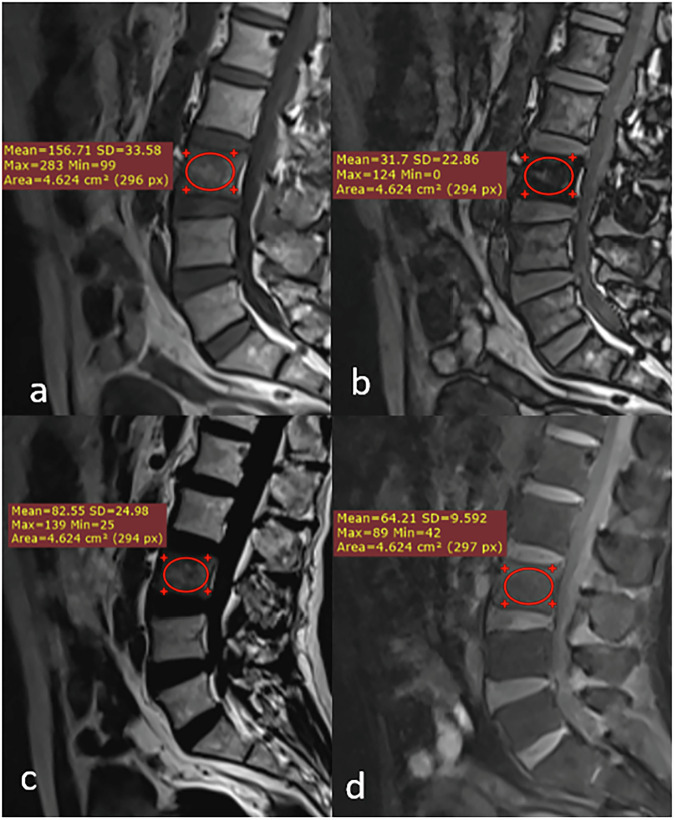

Materials and methods: In this prospective two-center study, 172 patients with BM signal abnormalities underwent standardized 1.5-T MRI protocols, including Dixon sequences. Two musculoskeletal radiologists independently evaluated images and performed quantitative measurements of %drop and %fat. Final diagnoses were established through histopathology (n = 96) or imaging follow-up (n = 76). Diagnostic value was assessed using area under the receiver operating characteristic curve (AUROC), inter-reader reliability using Cohen's κ coefficient.

Results: The consensus optimal cutoff was for %drop ≤ 19.8%, yielding 87.2% accuracy, 95.3% sensitivity, and 73.8% specificity, and that for %fat was ≤ 18.3%, achieving 86.6% accuracy, 96.3% sensitivity, and 70.8% specificity. Both metrics showed high diagnostic performance (AUROC 0.824-0.863) and excellent inter-reader reliability (κ > 0.93, p < 0.001). Multivariate analysis identified %drop ≤ 19.8% and %fat ≤ 18.3% as the strongest independent predictors of malignancy, with odds ratio (OR) being 9.38 and 8.85, respectively (p < 0.001). Signal characteristics on Dixon sequences provided additional diagnostic value, with signal voids on fat-only images (OR 7.14) and high signals on water-only images (OR 5.46).